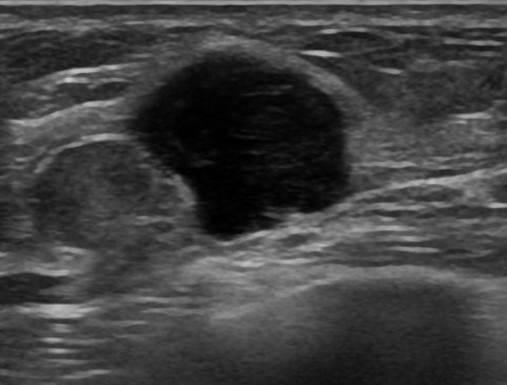

Ung thư vú

Ung thư vú - Ảnh 2

Ung thư vú - Ảnh 3

Ung thư vú - Ảnh 4

» Thông tin: Nữ giới – 55 tuổi.

» Lâm sàng: Khối tuyến vú.